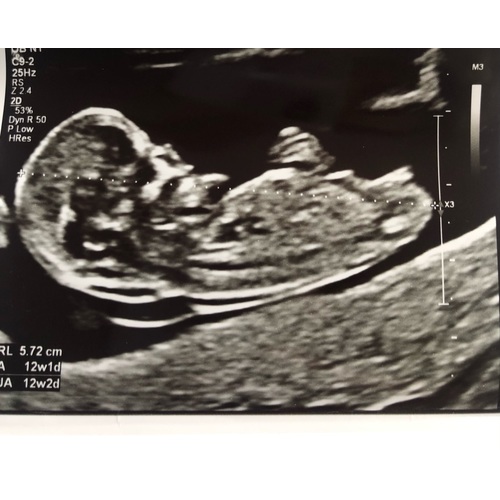

Hier een foto trouwens

Ze maakte er al mooie koprollen bij! Nu een heerlijk beweeglijk meisje 🥰